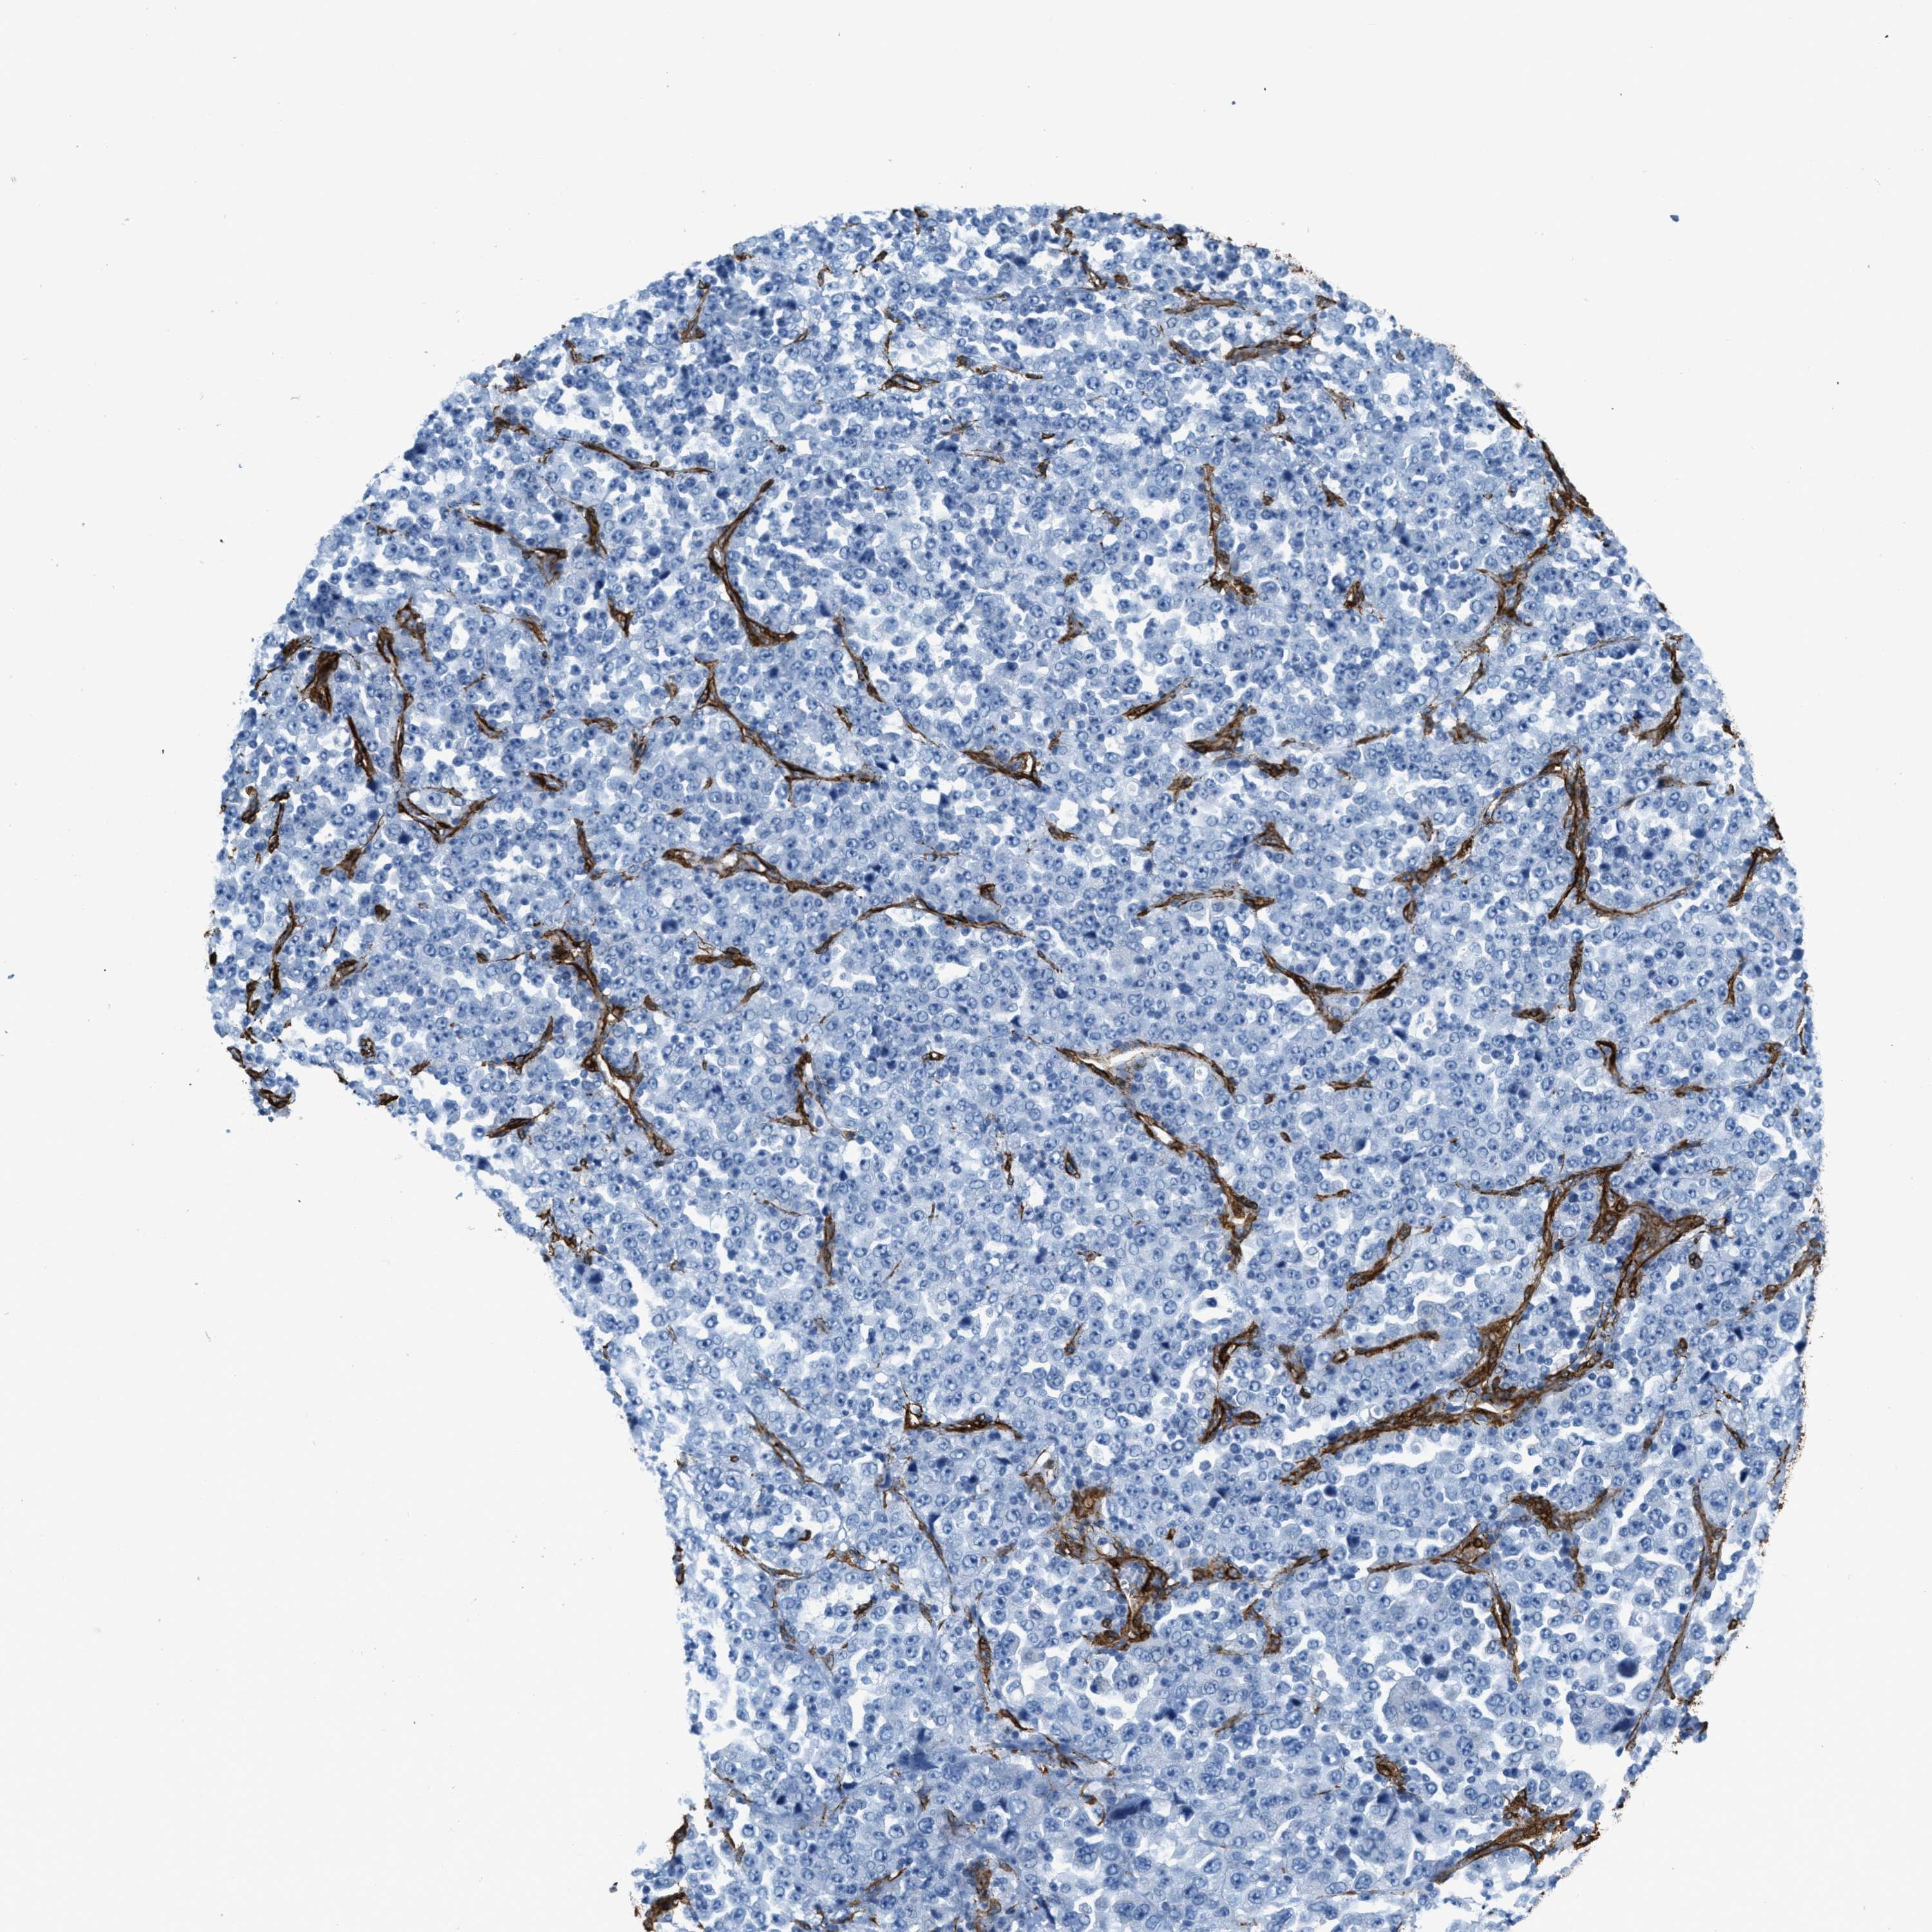

STOMACH CANCER - Protein expressioni

A mouse-over function shows sample information and annotation data. Click on an image to view it in a full screen mode. Samples can be filtered based on level of antibody staining by selecting one or several of the following categories: high, medium, low and not detected. The assay and annotation is described here.

Note that samples used for immunohistochemistry by the Human Protein Atlas do not correspond to samples in the TCGA dataset.

Antibody stainingi

Antibody staining in the annotated cell types in the current human tissue is reported as not detected, low, medium, or high, based on conventional immunohistochemistry profiling in selected tissues. This score is based on the combination of the staining intensity and fraction of stained cells.

Each image is clickable and will lead to virtual microscopy that enables deeper exploration of all samples and also displays staining intensity scores, fraction scores and subcellular localization as well as patient and tissue information for each sample.

Antibody HPA008066

Antibody HPA017330

Antibody CAB000006

Staining

High

Medium

Low

Not detected

Intensity

Strong

Moderate

Weak

Negative

Quantity

>75%

75%-25%

<25%

None

Location

Nuclear

Cytoplasmic/membranous

Cytoplasmic/membranous,nuclear

Adenocarcinoma, NOS